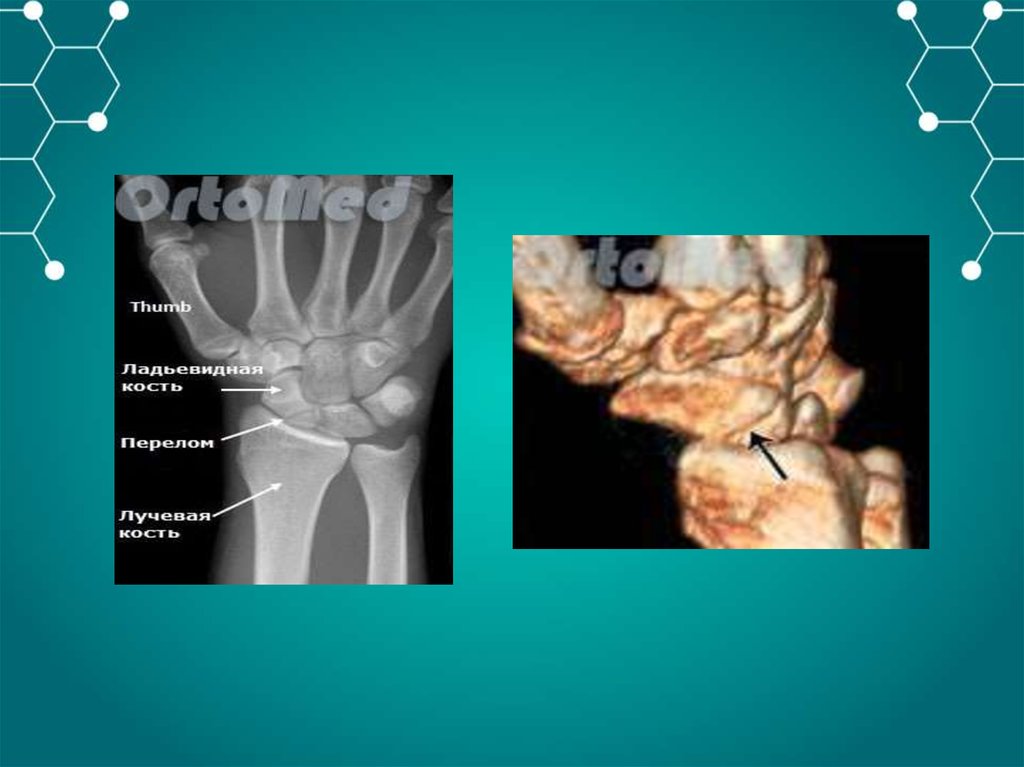

Частые перелом кисти